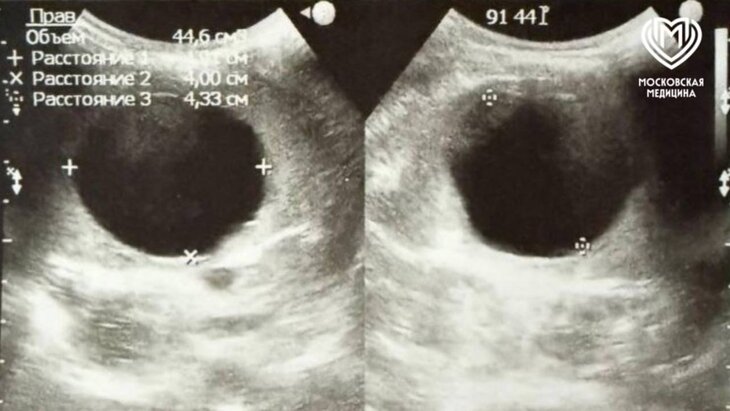

Столичные врачи удалили шестилетней девочке большую кисту селезенки

Хирурги Детской городской клинической больницы № 9 имени Сперанского удалили шестилетней девочке кисту, занимавшую большую часть селезенки. Об этом сообщила пресс-служба департамента здравоохранения Москвы.

"Исследования брюшной полости показали: киста занимает две трети селезенки и располагается возле крупных магистральных сосудов, которые кровоснабжают орган", – говорится в сообщении.

В Депздраве отметили, что чаще всего при подобных размерах кисты орган удаляют. Однако московским хирургам удалось сохранить ребенку селезенку. В настоящее время девочка уже выписана домой.